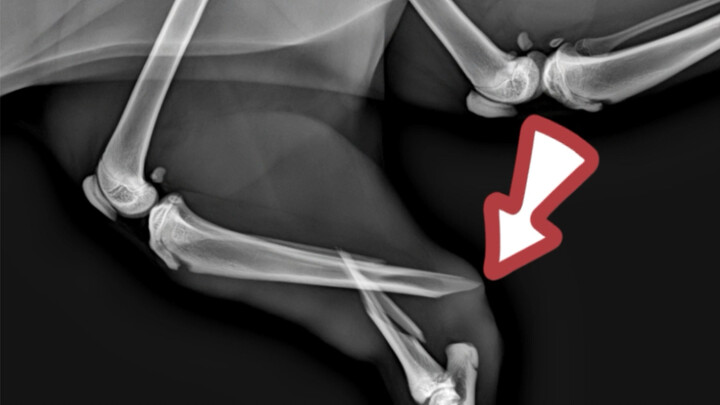

小狗误食别针和“💎”,过于疼痛导致无法自行排出,没划破肠胃真是万幸,你家宠物误食过哪些异物,评论区告诉我吧